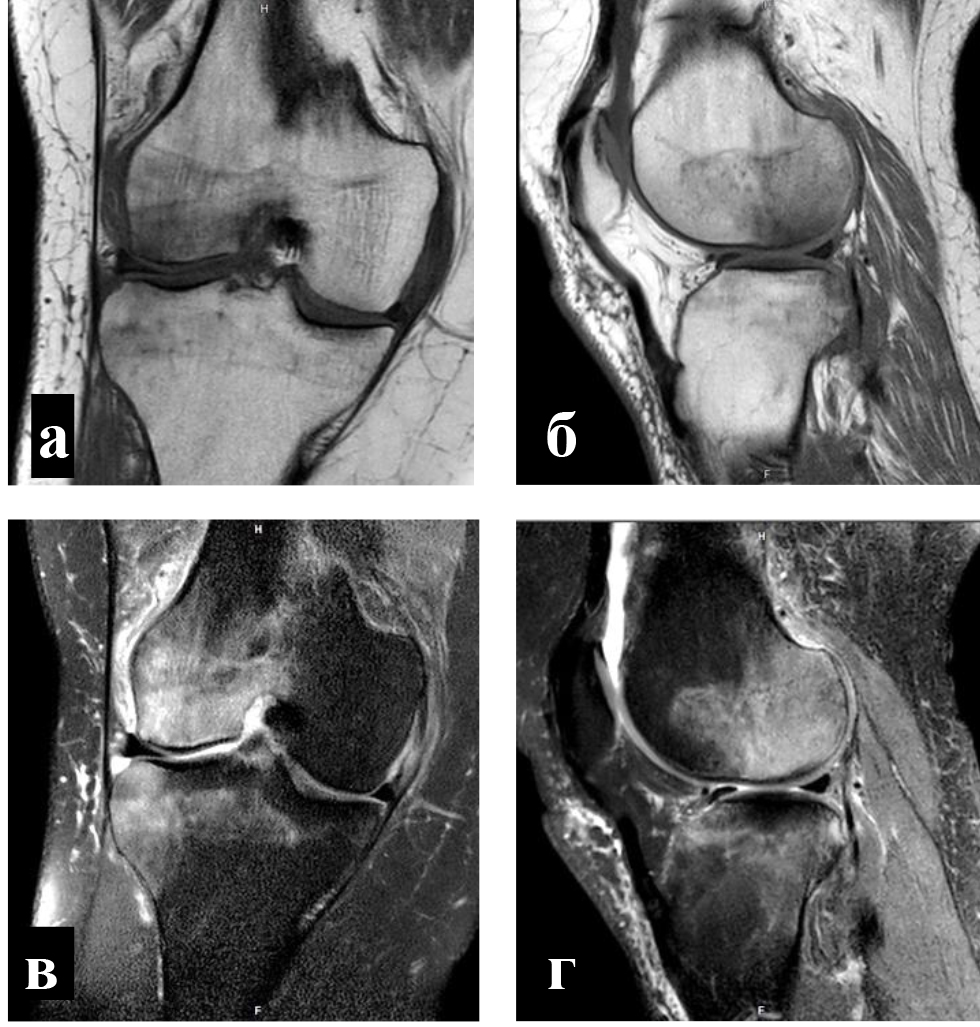

Внутрикостные инъекции ККМ и ОТП выполняли в условиях операционной. Используя 2%-й раствор лидокаина, инфильтрировали мягкие ткани по внутренней или наружной поверхности коленного сустава на 2 см проксимальнее и на 2 см дистальнее уровня суставной щели. Троакары вводили в кость вкручивающими движениями под углом 45 градусов по отношению к оси конечности и продвигали на глубину 1,5 см, достигнув субхондральных структур. Позиционирование троакаров оценивали с помощь электронно-оптического преобразователя (ЭОП) в 2 стандартных проекциях (рис. 3).

Рис. 3. Расположение троакаров при внутрикостном введении ККМ в область мыщелков бедренной и большеберцовой костей: a – расположение троакаров относительно уровня суставной щели (синяя стрелка); б, в – позиционирование троакаров в прямой и боковой проекциях под контролем ЭОП

Объективным показателем регресса болевого синдрома и нормализации клеточного метаболизма субхондральных структур являлось значительное сокращение объема или вовсе исчезновение зон трабекулярного отека костного мозга, что подтверждалось уменьшением гиперинтенсивных участков по данным МРТ (рис. 4) [8].

Рис. 4. Регресс трабекулярного отека костного мозга внутреннего мыщелка бедренной кости после введения ККМ: a – до введения; б – через 3 месяца